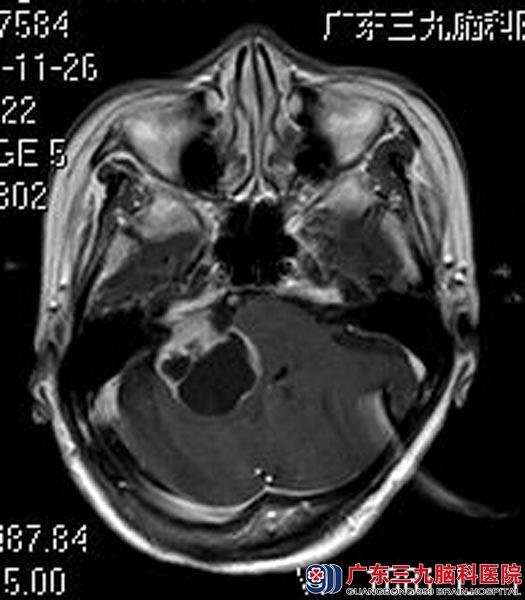

为进一步确诊,她来到广东三九脑科医院综合神经外科,头颅MR检查提示:右侧桥小脑角区占位性病变,约为34.0mm×35.1mm×35.2mm,脑干及右侧小脑半球受压,四脑室变扁,考虑听神经瘤可能性大,由于瘤的囊壁往往和面神经密切关联,手术分离具有一定难度,这也是考验医生对血管、神经解剖知识的熟练程度以及手术技巧的掌握程度。

术前